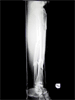

Segmental Tibia Fracture

Pre

Op

52year old Thai female with closed segmental fracture tibia following a road traffic accident